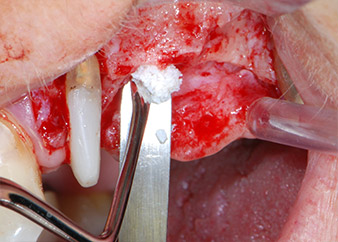

Prior to implant placement, and following verification of an intact Schneiderian membrane (Fig. 9), the internal sinus floor was augmented at both implant sites by means of xenogeneic bone substitute material (Bio-Oss, Geistlich Biomaterials) (Fig. 10).

Fig. 10: Introduction of xenogeneic bone substitute material into the implant osteotomy for internal sinus augmentation. The material was carefully condensed in an apical direction with the ball-ended CPITN probe (not shown).

Bone deficiencies around the implants, at the mesial aspect of tooth 27 and around the buccal root of tooth 24, were filled with xenogeneic bone substitute particles and covered with an absorbable collagen membrane (Bio-Gide, Geistlich Biomaterials) for GBR augmentation (Figs. 13 and 14).

Xenogeneic bone substitute material

Fig. 13: Xenogeneic bone substitute material was used to fill the remaining osseous defects …

absorbable collagen membrane

Fig. 14: ... which was then covered with an absorbable collagen membrane. The grayish-pink structure between the elevators at the top margin of the picture represents interproximal papillary tissue.